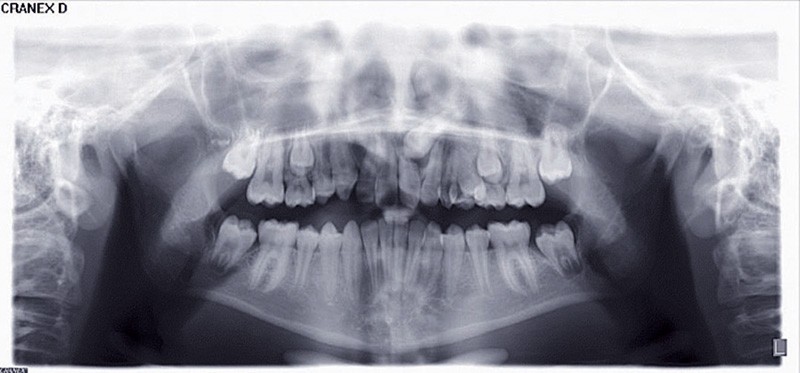

Rappel de la problématique. Mademoiselle O. âgée de 13 ans en classe I squelettique mésodivergente présente la persistance de 63. La panoramique et l’examen tomodensitométrique montrent une transposition de la 23 qui évolue au-dessus de la 21 et a entraîné une résorption radiculaire de celle-ci.

D’après les documents fournis, il s’agit d’une transposition de 23, transposition partielle, l’apex étant en bonne position (fig. 1).

Il n’y a aucune autre image suspecte de la denture, pas d’anomalie de développement des dents, tout juste des apex plutôt fins. La racine de 22 est intacte, les autres dents visibles sur le document ne montrent pas de résorption apicale. La 63 est intacte avec une longue racine non résorbée.